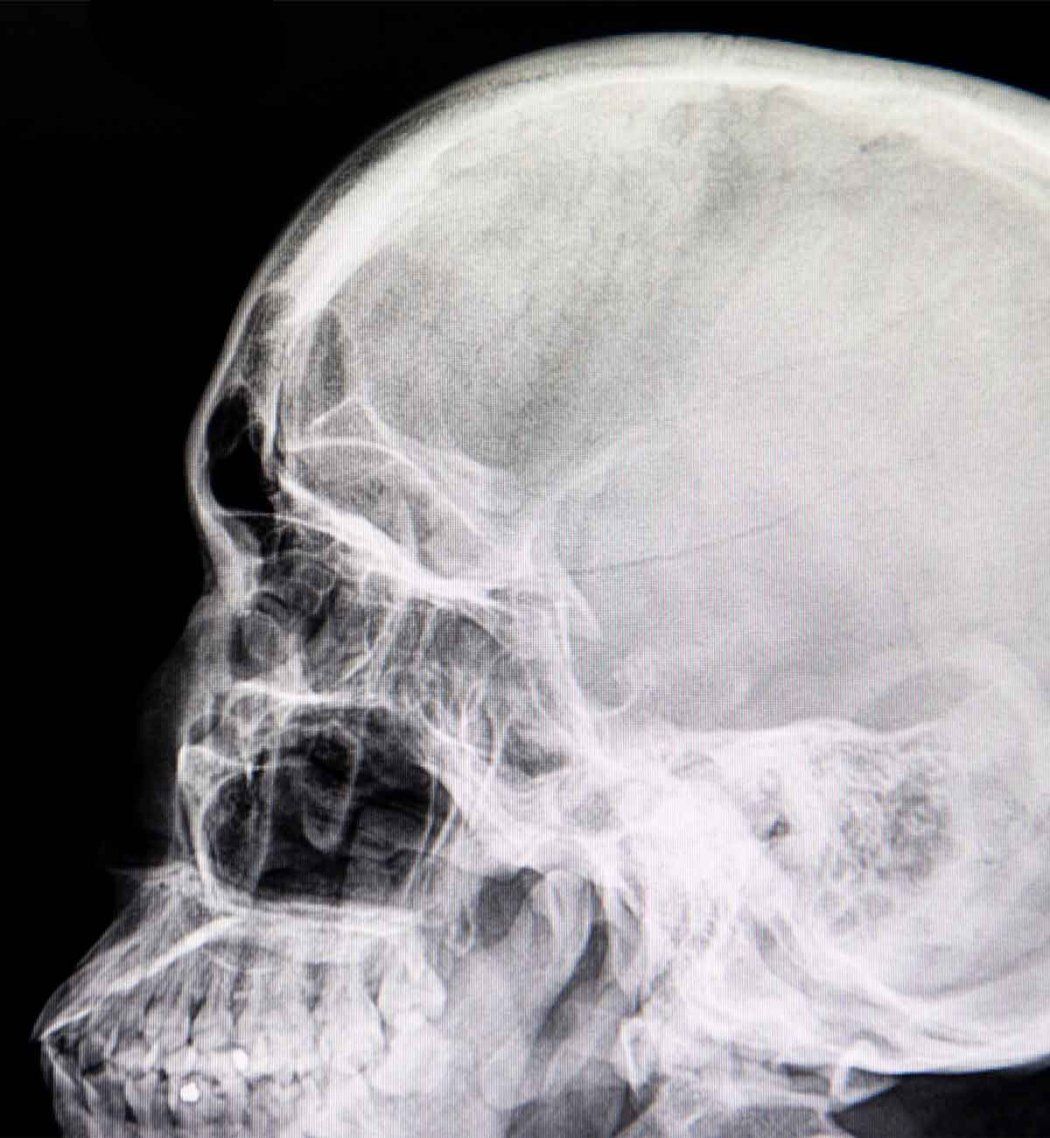

Significantly, low levels of these biomarkers determine which patients do not require CT scans, reducing unnecessary radiation exposure and health care costs. These patients can then be discharged. In those with more severe injuries, CT and MRI imaging — the framework’s third pillar — are important in identifying blood clots, bleeding, and lesions that point to present and future symptoms.

Two brain scans featuring brain injury.

These images show how treatment is impacted by the new TBI framework. The left image shows a clear CT, but a higher biomarker level and a brief period of amnesia and other symptoms would result in follow-up and symptom-targeted treatment.

The right image shows bruising (red arrow) and bleeding between the brain and membranes surrounding it (yellow arrow). The new framework reveals a higher biomarker level, bipolar disorder, prior TBI, and unemployment. This patient would be referred to mental health and social services, as well as other programs to help her manage risk factors.